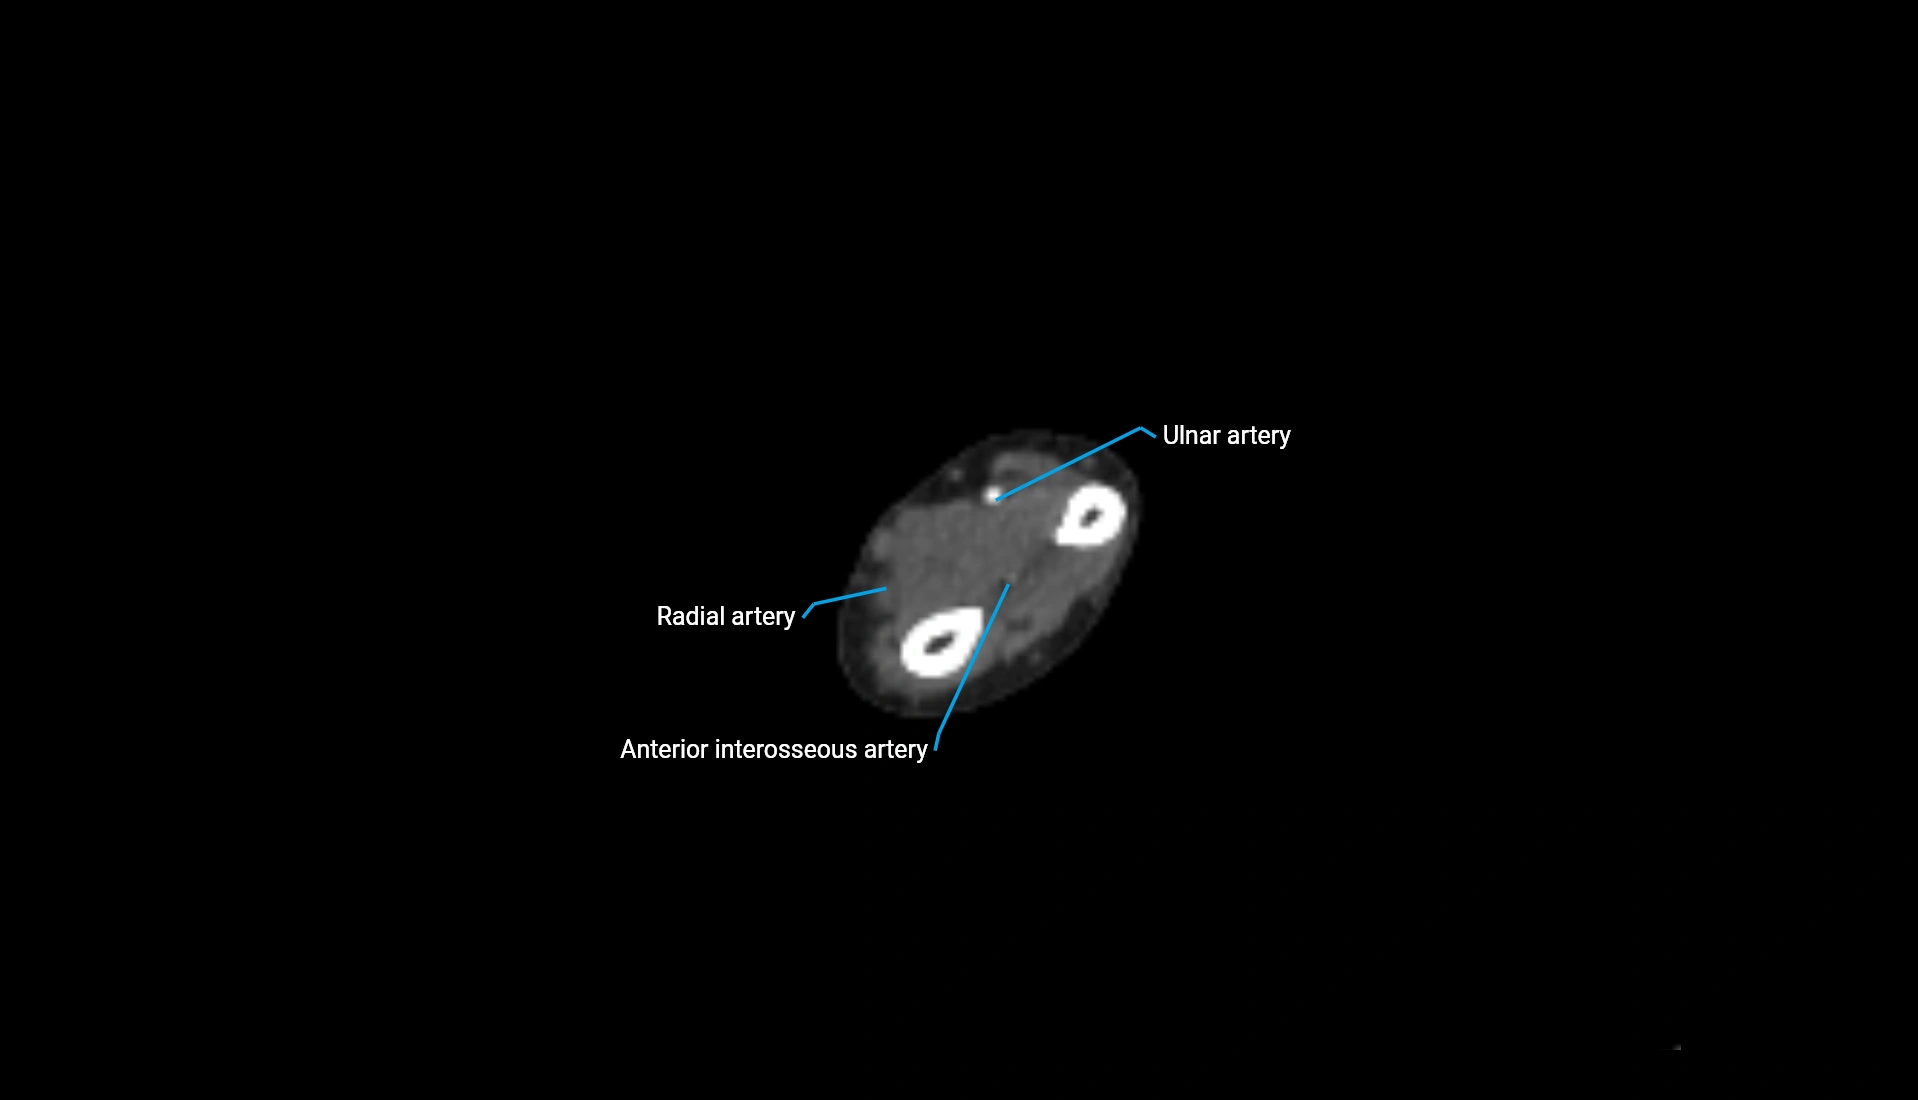

MRI image

image